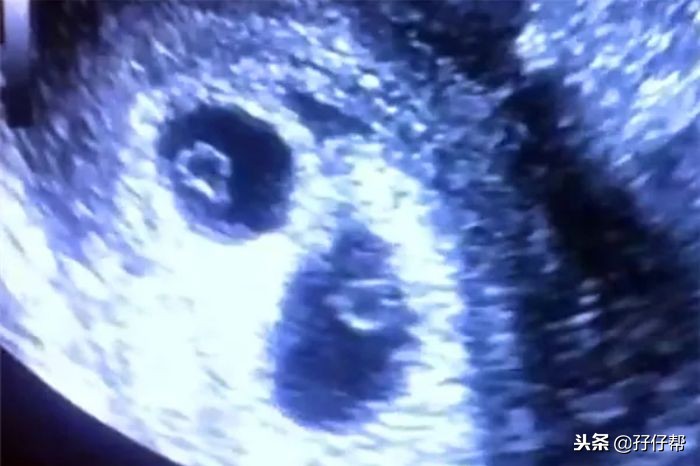

B超孕6周的双胞胎胎儿影像图⬇⬇

据说,这个孕周的胎儿心脏开始扑通扑通地跳动,如果此时去做B超就会发现两个胎心胎芽。